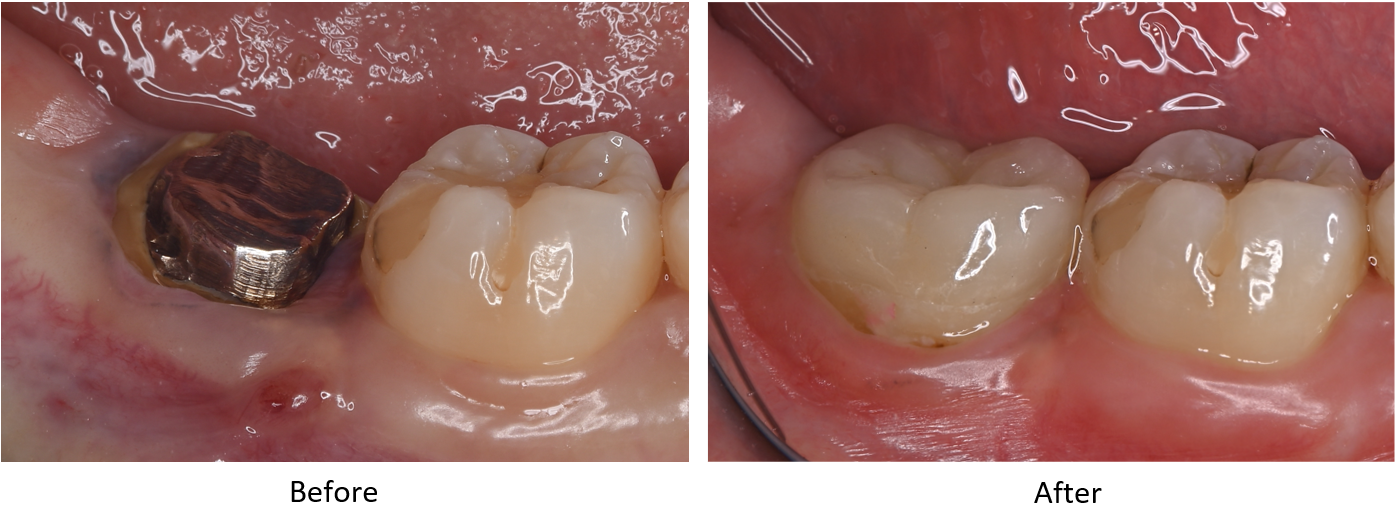

症例3

治療の流れ

| 患者様データ | 40代 女性 |

| 来院時の主訴 | 「左側奥歯で噛むと痛い。」 |

| 医院の診断 | 歯根破折、慢性根尖性歯周炎 |

| 通院期間 | 6か月 |

| 来院回数 | 9回 |

| 治療費 | 総額:330,000円(税抜) 【内訳】 歯牙移植150,000円、ファイバーポストコア20,000円、ダイレクトボンディング80,000円×2 |

| リスクと副作用 | ①根管治療歯は長期的には破折するリスク ②長期的なメインテナンスが必要 ③歯根の外部吸収 |

| ここがこだわりのポイント!☝ |

抜歯が必要になった際に余っている親知らずがあれば移植歯として利用することができます。 術前に撮影したCT画像から3Dプリンターを用いて親知らずのレプリカを作製することで、親知らずが乾燥することを防ぎ、成功率が上がるよう努力しています。 |